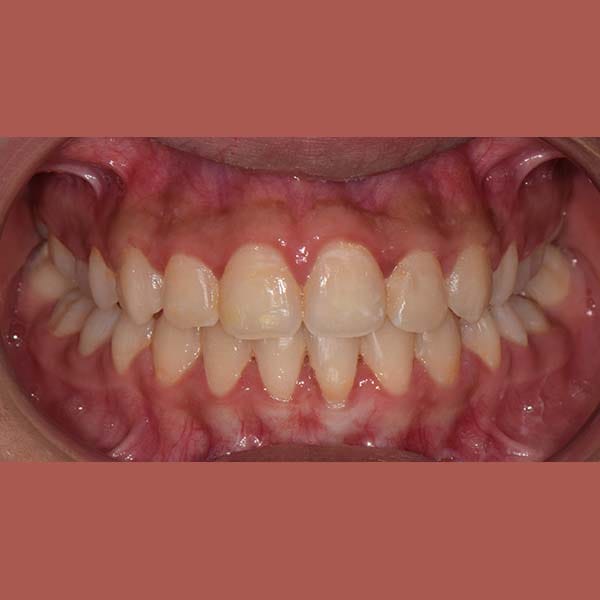

BEFORE

This girl suffered from severe upper jaw stenosis, which negatively affected her smile,

suppressed the beauty of her white teeth when smiling, and also led to a buried upper-right canine in the bone, and a reverse bite in the back teeth.